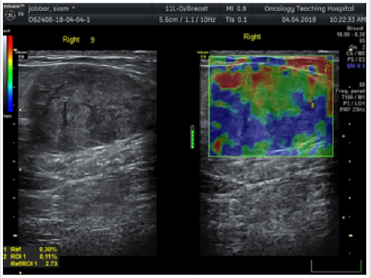

In this study: Fibroadenoma, simple cyst, and fibrocystic changes were the foremost common benign lesions whereas infiltrative ductal carcinoma was the foremost common malignant lesion. Fibroadenomas showed up smooth oval or adjusted in shape with well-defined edges, homogenous echotexture, isoechoic with bilateral acoustic shadowing, wider than taller and either softer than or had the same elasticity as adjoining glandular tissue with score 1, 2 or 3 (Figure 1). Fibroadenomas sometimes have size and stiffness pattern by elastography which is similar to that of malignant lesions as in calcified fibroadenomas with elasticity score 3 or 4 (Figure 2). Malignant breast lesions are speculated, irregularly formed, unwell outlined, with heterogeneous echotexture, distorted design, central shadowing, taller than wider, small calcifications, elastography score 4 or 5. They appeared larger on the elastography image due to higher visualization of the encircling desmoplastic reaction (Figures 3 & 4).

Figure 3: 33 years female with a single right palpable breast lump.

a) The conventional US showed well outlined hypoechoic focal lesion with multiple calcifications

b) On elastography: the lesion showed a heterogeneous however largely green and blue colors signature with elastography score four. The diagnosing was confirmed to be fibroadenomas.